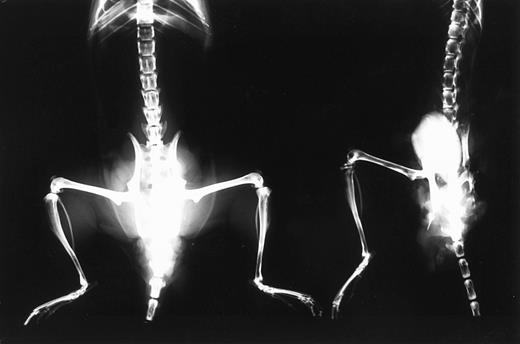

Bone resorption.Because bone resorption and extramedullary invasion of tumor cells are often induced in advanced MM, the appearance of hind leg paralysis in the mice was thought to be caused by compression of spinal cord by the tumor mass. X-ray photography showed that bone density of mice with advanced tumor growth was decreased throughout their bodies (Fig 3). Some of these mice showed obvious fractures in the femur (data not shown).

X-ray photographic observation of bones in mice 37 days after IV inoculation with KPMM2 cells. Decrease in bone density was observed in the tumor bearing mouse (right) in comparison with normal mouse (left).

X-ray photographic and histologic observation showed a decrease of bone density in the whole body and osteolytic lesions around osteoclastic polynuclear cells. Several cytokines including IL-6 are known to stimulate osteolysis through direct or indirect activation of osteoclasts.31 32 Therefore, IL-6, secreted by KPMM2 cells, may play an important role for bone absorption in this model.